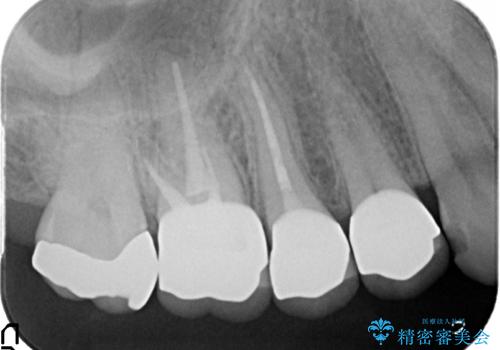

- ものを咬むと右上の歯が痛むといらっしゃった方の症例です。

検査の結果右上5の歯の神経が死んでいたため、根管治療を行った後に、オールセラミッククラウンによる補綴を行いました。

また右上6に関しては再根管治療を行い、右上4に関しては虫歯治療を行った後に、オールセラミッククラウンによる補綴を行いました。